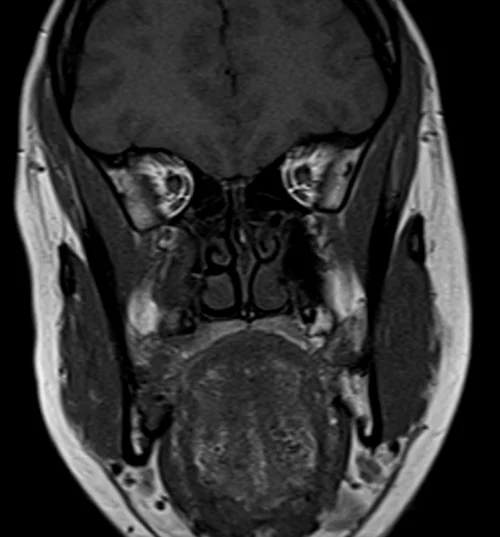

Orbits

BRAIN ORBITS